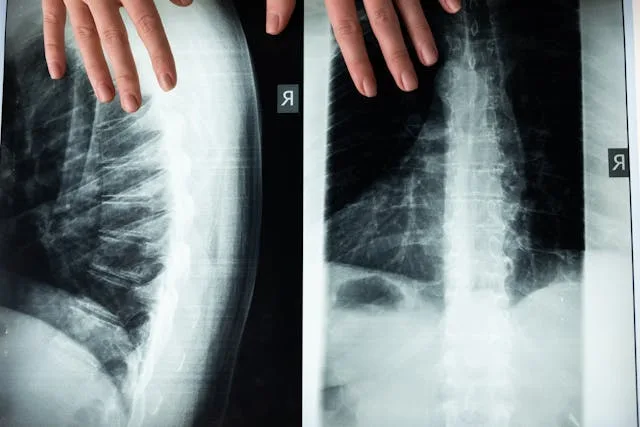

Procene kičmenog stuba

Rendgen kičmenog stuba